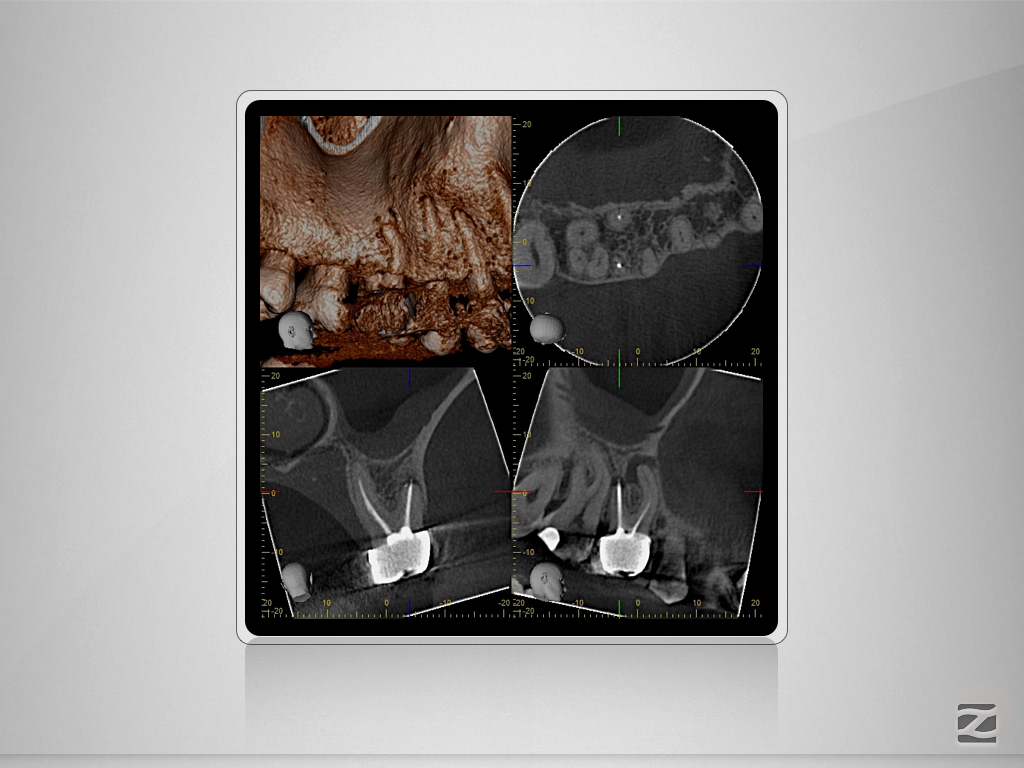

16D.004

1024 × 768

Von allem etwas …